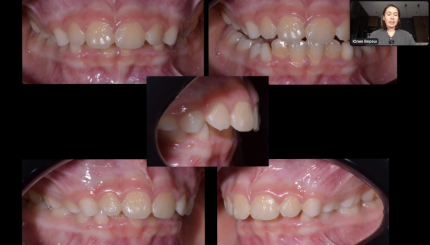

Клинический случай. Ребенок, II класс

Разбор кейса. MLD, ребенок, техника направленного роста